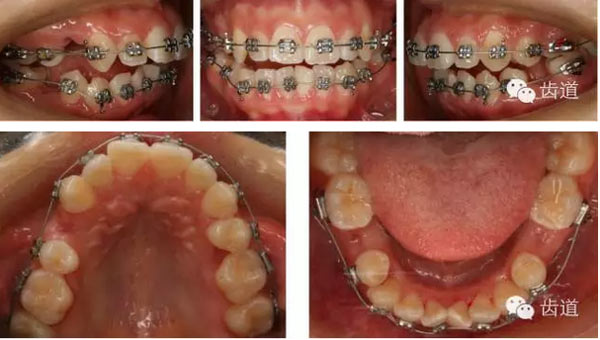

矯治結(jié)束后口內(nèi)像

治療前后口內(nèi)相對(duì)比

拔牙模式:患者25腭側(cè)完全錯(cuò)位后左上磨牙前移,使左側(cè)磨牙關(guān)系接近完全遠(yuǎn)中,而28牙冠較小,故正畸矯治拔除了14,18,25,28,35,45,于上頜第一與第二磨牙間頰腭側(cè)各植入微種植體支抗,運(yùn)用微種植體支抗壓低上磨牙,內(nèi)收前牙并糾正中線,適當(dāng)遠(yuǎn)中移動(dòng)左上牙列。下頜第三磨牙矯治前并未拔除是因?yàn)槠渖L(zhǎng)對(duì)矯治有利,建議其矯治后拔除。

橫向不調(diào):牙弓寬度輕度不調(diào)的解決在于上頜適當(dāng)?shù)臄U(kuò)弓與后退左上牙列,以及下頜適當(dāng)?shù)目s弓與下磨牙前移,矯治后上頜磨牙寬度由41.8mm變?yōu)?3.1mm,下頜磨牙寬度由39.6mm變?yōu)?7.8mm。

矢狀向、垂直向及開(kāi)合:上頜磨牙壓低及下頜磨牙前移產(chǎn)生的楔形效應(yīng),上前牙適量?jī)?nèi)收產(chǎn)生的鐘擺效應(yīng),以及肌功能訓(xùn)練的綜合作用解除了患者的開(kāi)合,并使下頜逆時(shí)針旋轉(zhuǎn),矯治后患者的側(cè)貌得到極大改善,達(dá)到了近乎“頦成形”的效果。